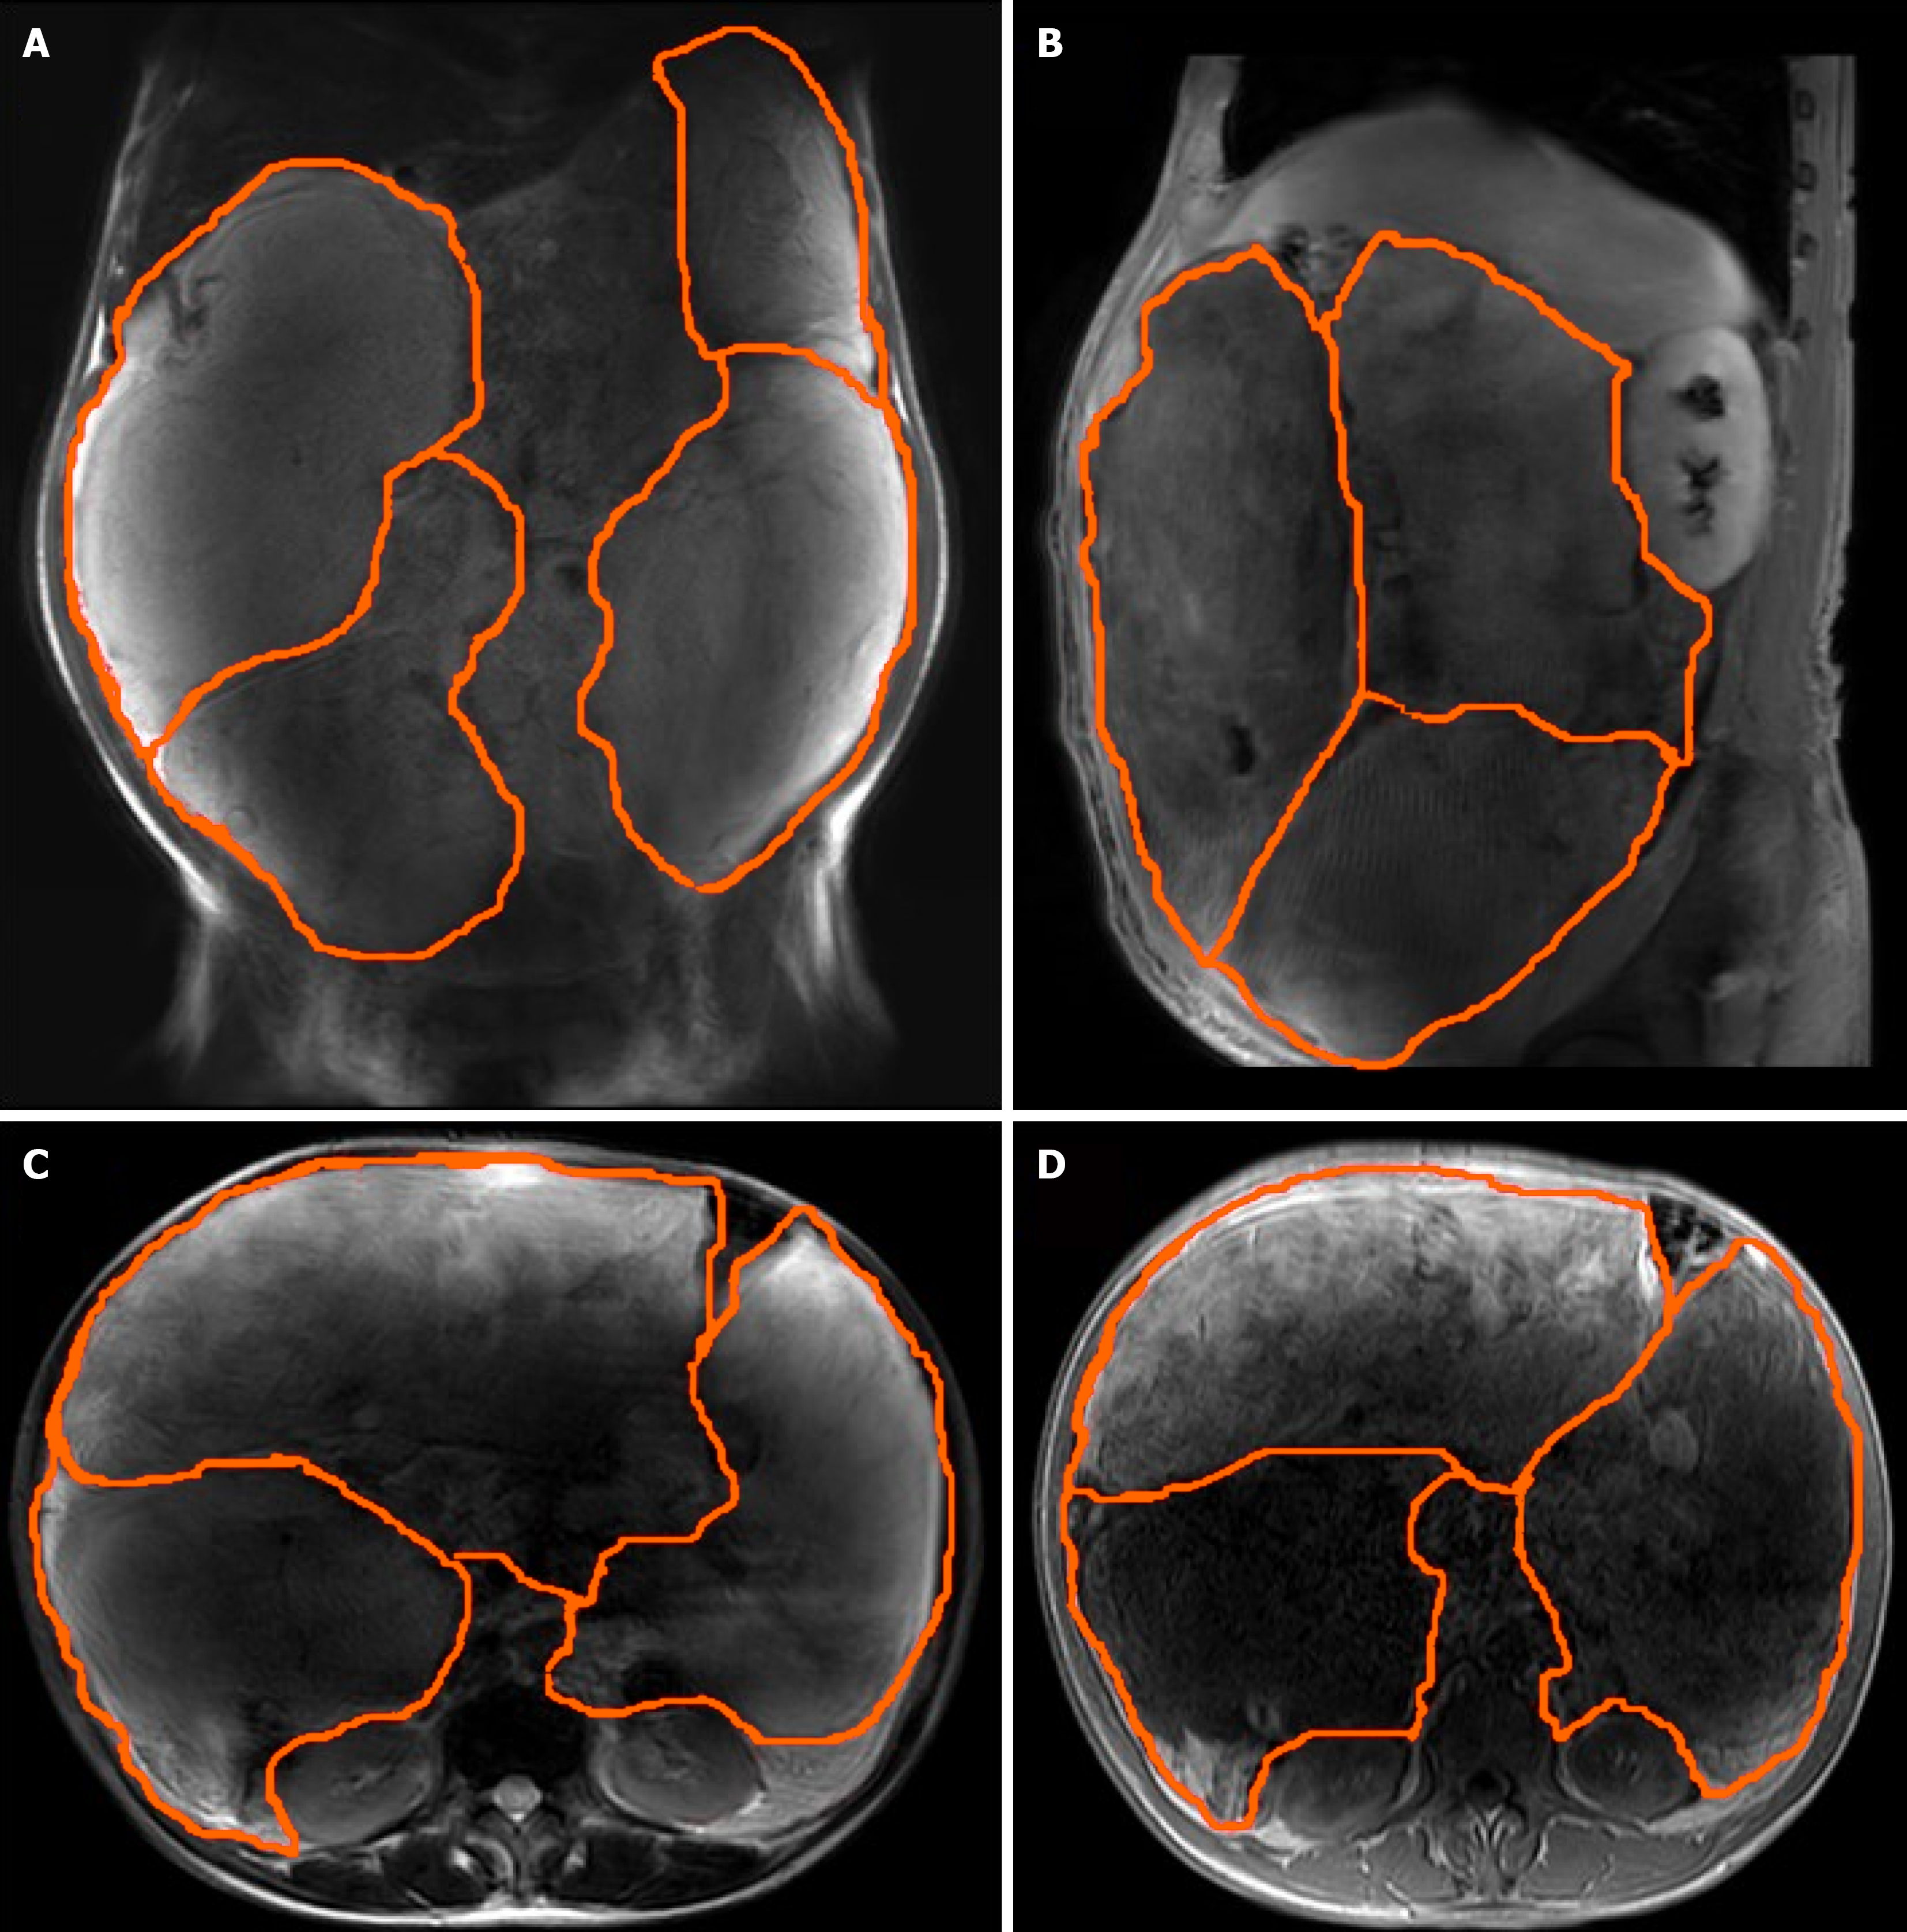

Abdominal ultrasound at another hospital manifested an abdominal giant mass in the abdomen in which the origin is unknown. CT scan of the chest at our hospital indicated that no lesions of metastasis were found. Abdominal enhanced CT examination at another hospital detected a large, solid abdominal mass that almost entirely occupied the abdominal cavity. Abdominal and pelvic magnetic resonance imaging at our hospital was completed, which showed that multiple round masses were found in the abdominal cavity with an envelope. The mass originated from the mesentery. It was also well circumscribed, lobulated, heterogeneous, and compartmentalized, with a maximum size of 25 cm × 23 cm × 15 cm (Figure 2). The mass removed intraoperatively was isolated, with a maximum size of 25 cm × 23 cm × 15 cm, and all masses were approximately 11 kg in weight (Figure 3A). The mass cut surface was soft, with a white-to-yellow color (Figure 3B). The histopathological examination of the specimens revealed that the tumor composed of atypical cells. In the focal areas, WDLPS was observed. Immunohistochemistry staining showed that the leucocyte antigen was positive on MDM2, S-100, P53, P16, Vim, and Ki-67 (3%) tumor cells and negative on EMA and CK-pan (Figure 4). Given these fin